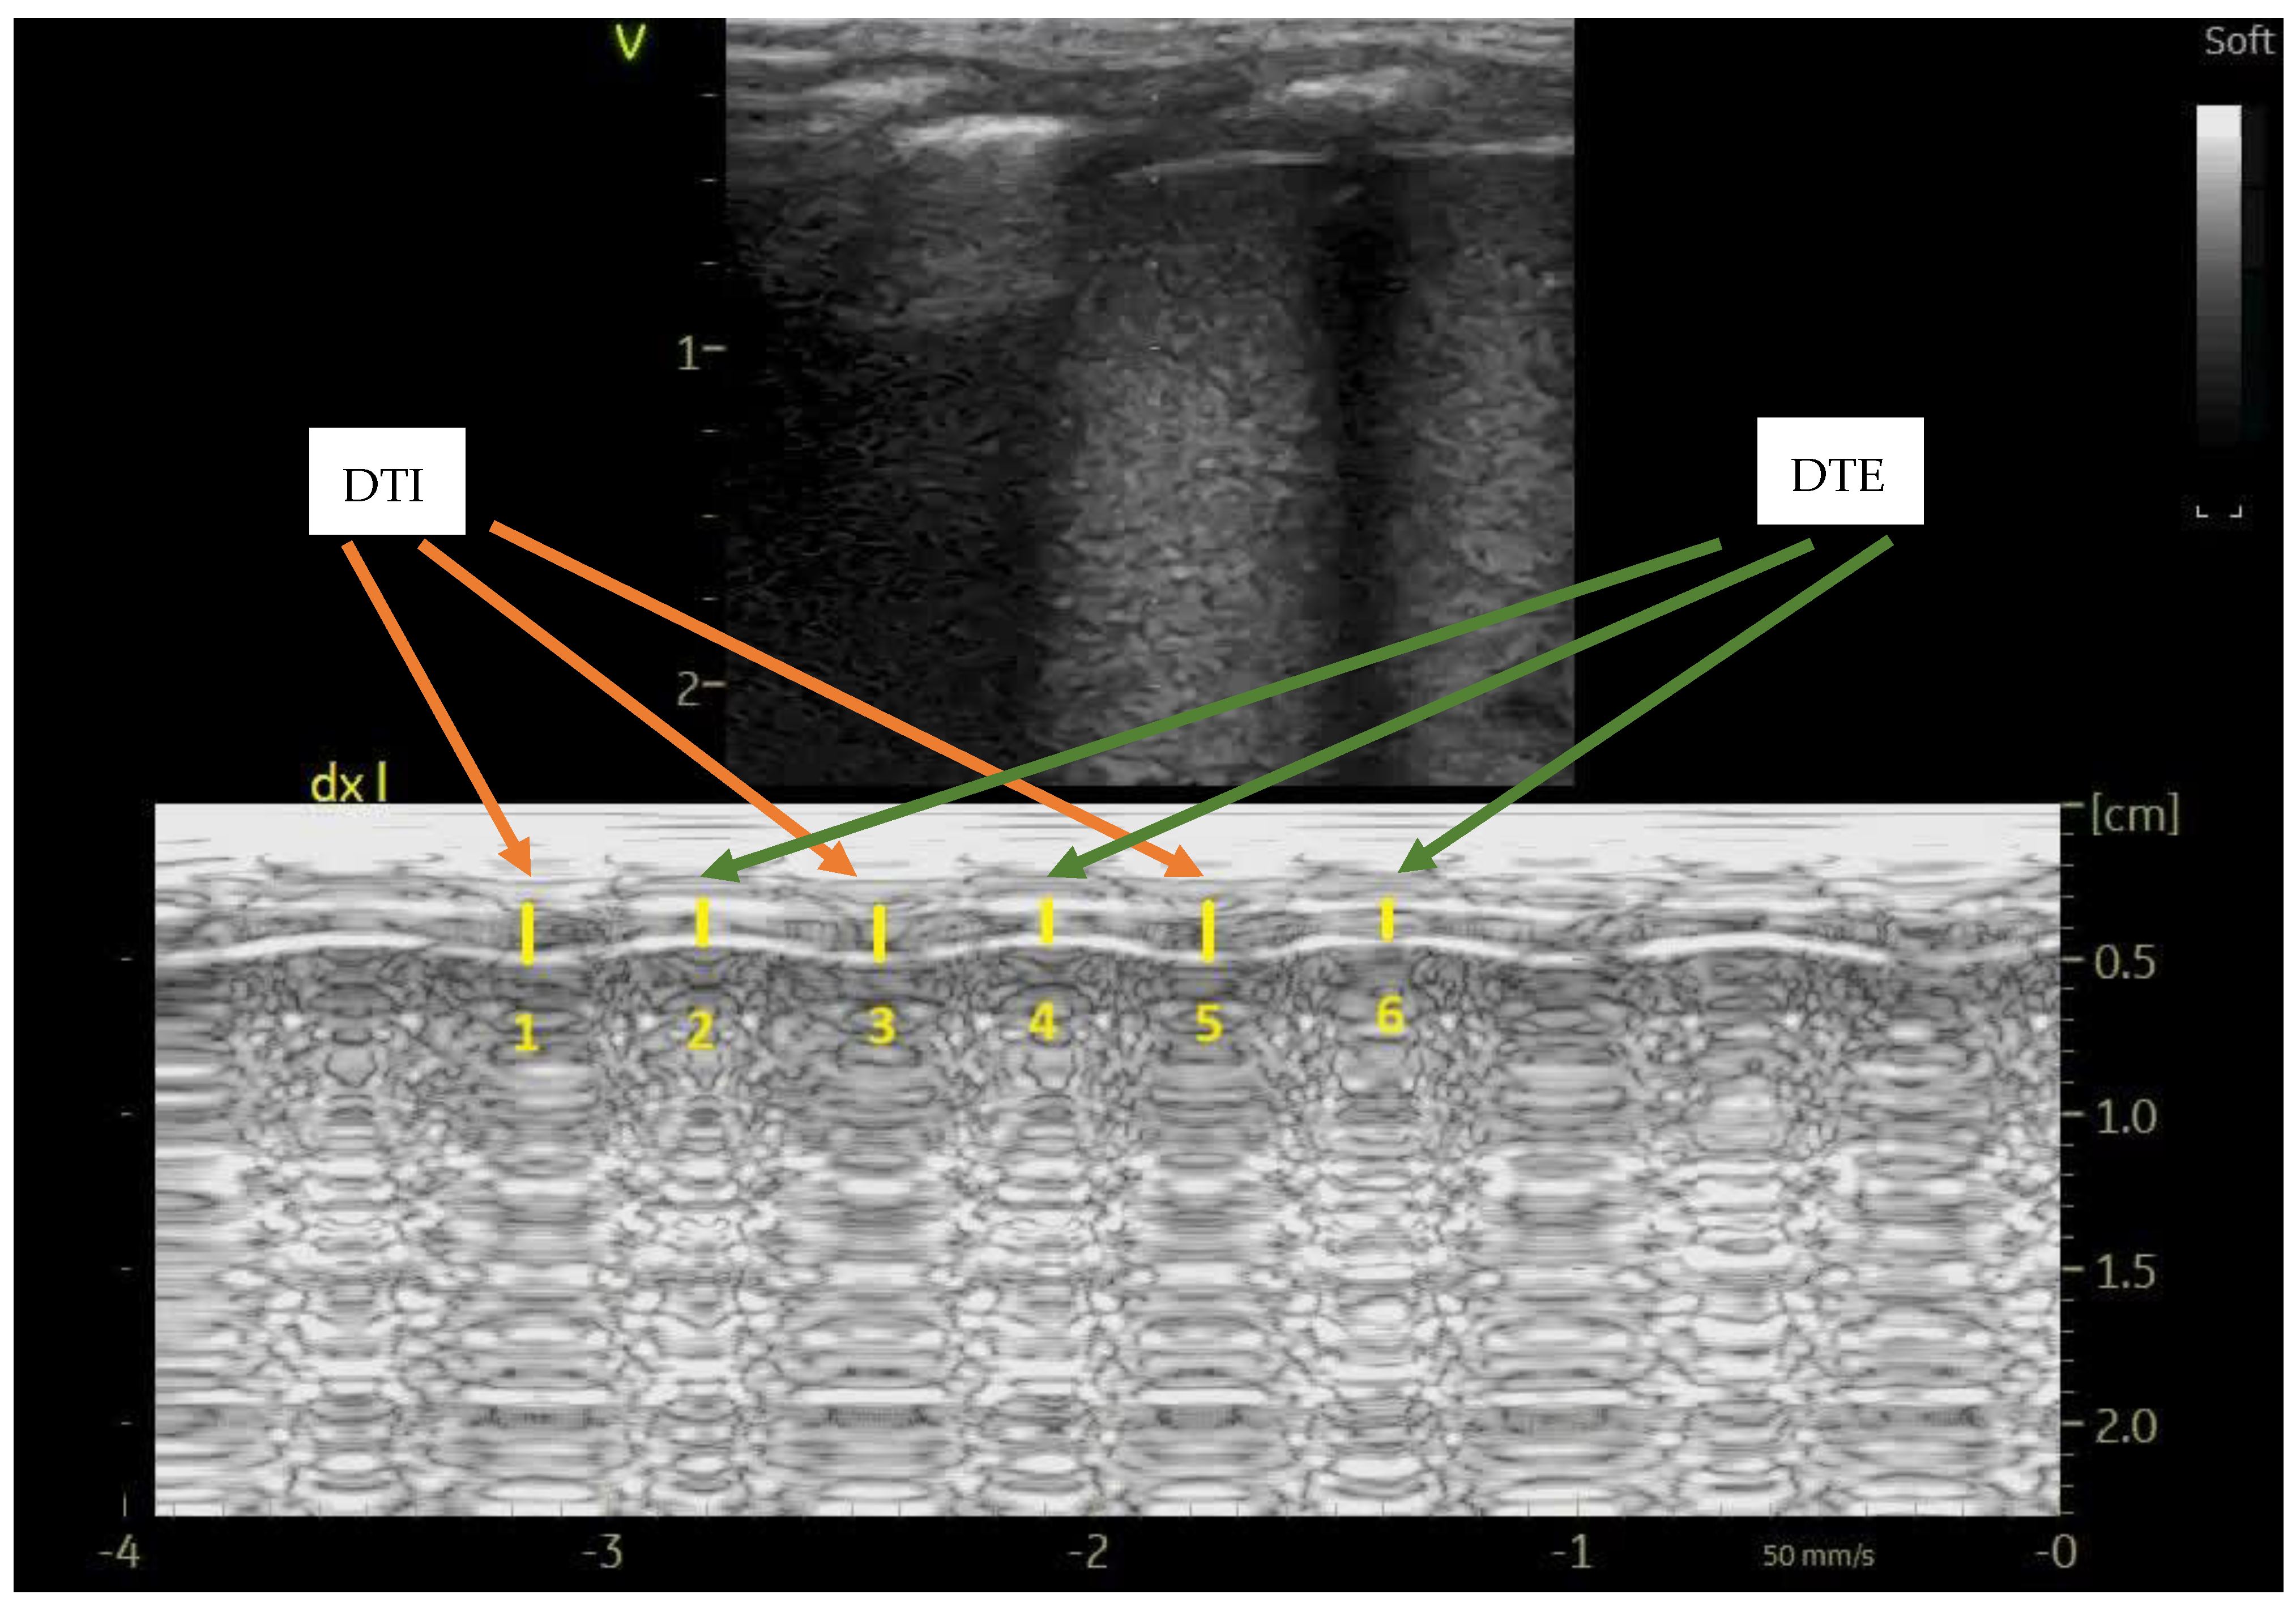

Diaphragm thickness at end-inspiration (DTI) and end-expiration (DTE) were recorded, and diaphragm thickening fraction was calculated as (DTI-DTE)/DTE; at least three measures in M-mode were averaged, as depicted in Figure 1; diaphragm atrophy during mechanical ventilation was defined as ≥ 10% decrease in DTE [9].

Figure 1. Diaphragm ultrasound in M-mode showing the DTI (average value of measures number 1, 3 and 5) and DTE measurements (average value of measures number 2, 4 and 6). The probe was longitudinally applied on the right mid-axillary line (diaphragm apposition zone).